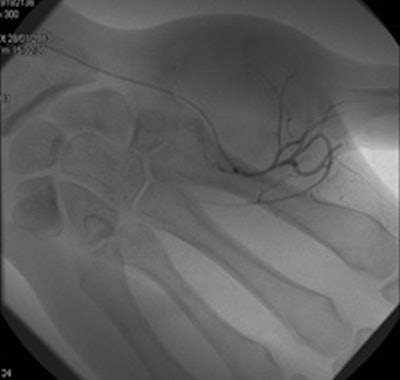

Bilbao's keen interest in interventional radiology began during the third year of his residency in 1982.

In the third year of my residency in 1982, I began to be attracted by the new way to perform interventions through percutaneous and endovascular approaches, and for a few months I went to the MD Anderson Center in Houston, Texas, U.S. There I took an important decision, which was that I would like to be completely involved in interventional radiology (IR), and with the great support of the CUN, this is what I have done for the rest of my professional life.